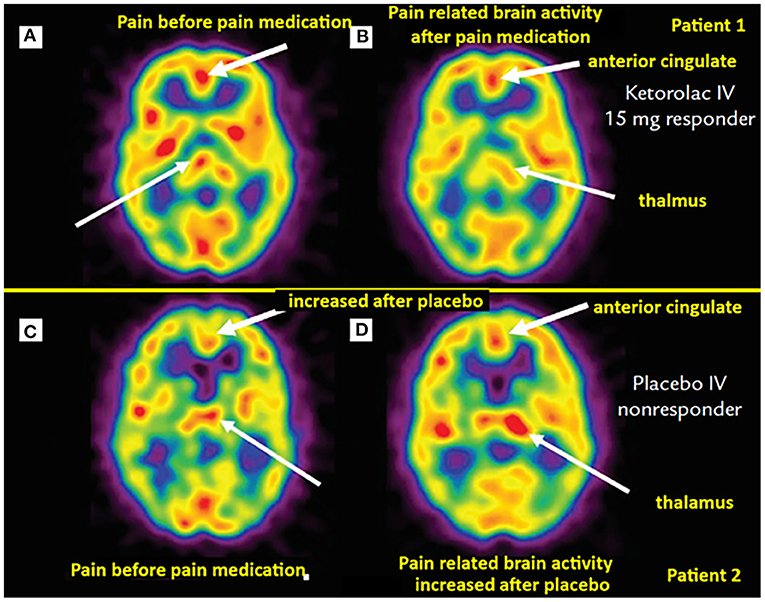

Scientists have used advanced brain imaging to watch what happens during placebo responses. The results are remarkable, showing concrete changes in brain chemistry and activity patterns.

Studies have shown that placebo-induced analgesia, for example, involves the release of endorphins and other natural painkillers in the brain, which can reduce pain perception like that of actual analgesic drugs. Think of it this way: your brain has its own pharmacy, and positive expectations can unlock it. The neurochemical systems implicated in placebo analgesia include opioid, dopamine, serotonin, cholecystokinin, and oxytocin systems.

When a patient expects to get better, the brain initiates a cascade of cognitive and neural processes to match that expectation, recruiting the prefrontal cortex to modulate pain processing before the medicine even dissolves. Your expectations literally shape your physical reality.